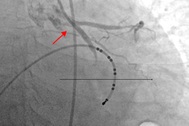

Sau khi được cho nhập viện, bệnh nhân biểu hiện môi tái, mạch bắt nhẹ, huyết áp thấp rồi sốc tim, rồi loạn nhịp tim và ngưng tim. Ngay lập tức, ekip điều trị đặt nội khí quản, xoa bóp tim ngoài lồng ngực và kích hoạt báo động đỏ để thực hiện chạy ECMO (tim phổi nhân tạo) cấp cứu cháu bé.

Bé gái sốc tim, ngưng tim nguy kịch khi vào viện (Ảnh: BV).

Sau khi chạy ECMO giúp huyết động bệnh nhân tạm ổn định, bé gái phải dùng thêm thuốc trợ tim, thuốc chống loạn nhịp tim và lọc máu liên tục. Bên cạnh đó, bệnh nhi cũng được thực hiện kỹ thuật hạ thân nhiệt chủ động kèm dùng thuốc chống phù não để bảo vệ não.